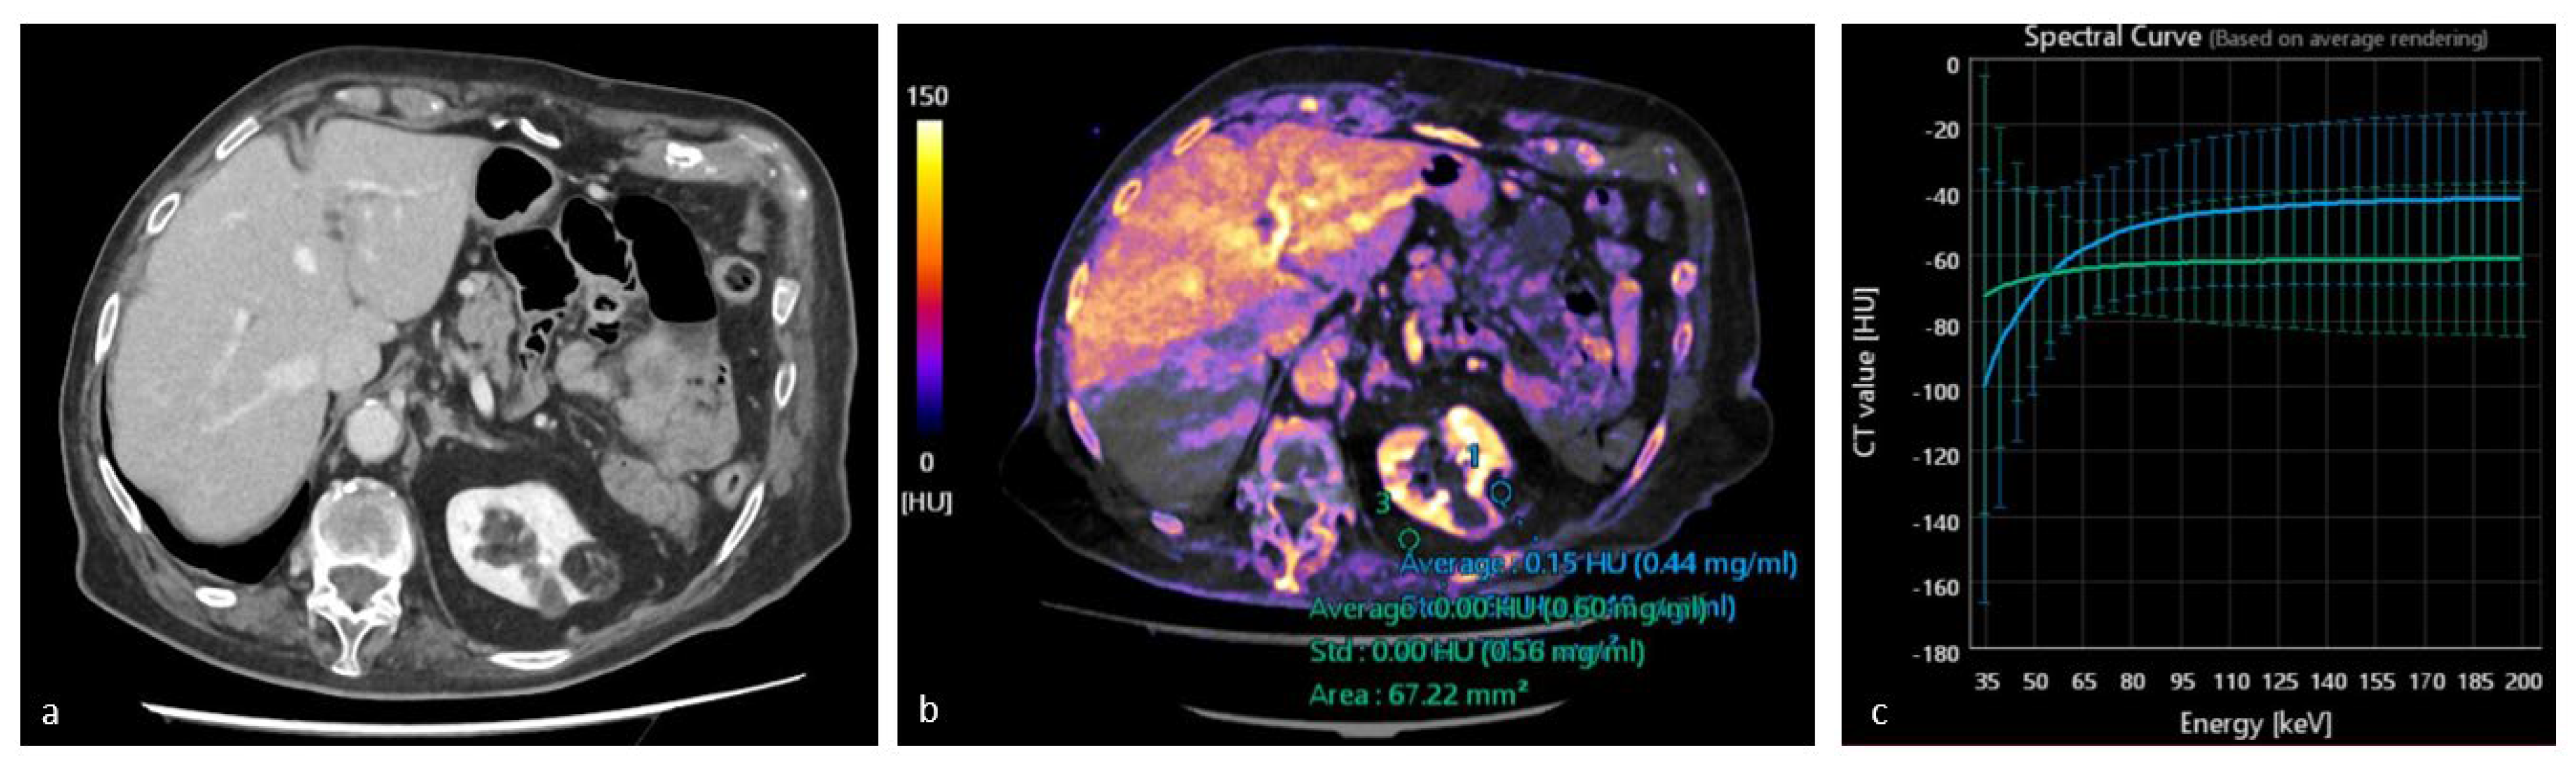

3.3. Iodine Maps

3.4. Spectral HU Curves